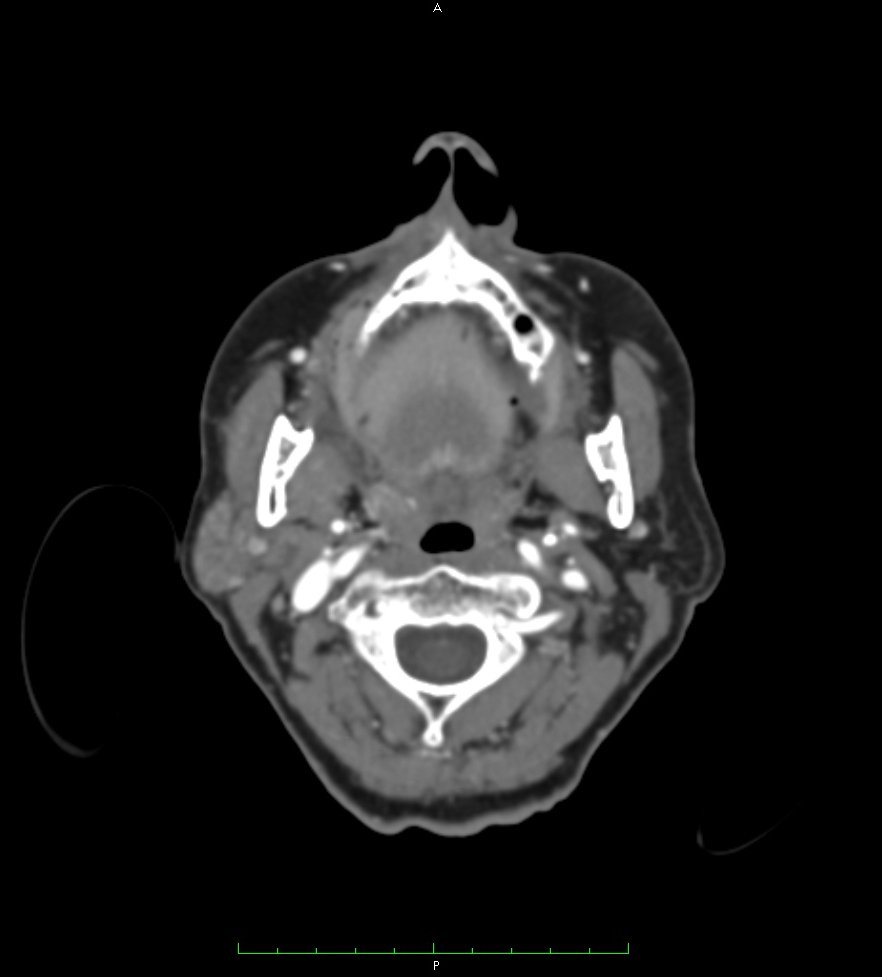

MRI combined with image processing pipelines provide a powerful tool to inform doctors how to treat arrhythmias. Visualizations can help providers plan intervention and then to communicate findings and care plans to the patient.